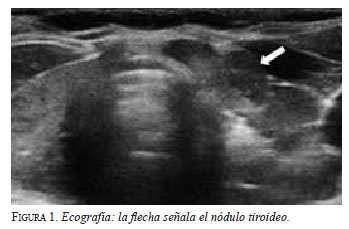

En el Hospital General de Castellón, la PAAF es practicada por los radiólogos, sea palpable o no palpable la lesión. Se selecciona el lugar más adecuado para la punción mediante ecografía o tomografía axial, se limpia la piel con una solución yodada y se aplica anestesia. La posición de la aguja es seguida por imagen, para evitar vasos sanguíneos y minimizar el riesgo de sangrado. Se utilizan agujas de 22G, que permiten obtener muestras tisulares pequeñas10,11 (figura 1).